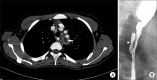

Esophageal candidiasis is commonly seen in immunocompromised patients; however, candida esophagitis induced stricture is a very rare complication. We report the first case of esophageal stricture secondary to candidiasis in a glycogen storage disease (GSD) 1b child. The patient was diagnosed with GSD type 1b by liver biopsy. No mutation was found in the G6PC gene, but SLC37A4 gene sequencing revealed a compound heterozygous mutation (p.R28H and p.W107X, which was a novel mutation). The patient's absolute neutrophil count was continuously under 1,000/µL when he was over 6 years of age. He was admitted frequently for recurrent fever and infection, and frequently received intravenous antibiotics, antifungal agents. He complained of persistent dysphagia beginning at age 7 years. Esophageal stricture and multiple whitish patches were observed by endoscopy and endoscopic biopsy revealed numerous fungal hyphae consistent with candida esophagitis. He received esophageal balloon dilatation four times, and his symptoms improved.